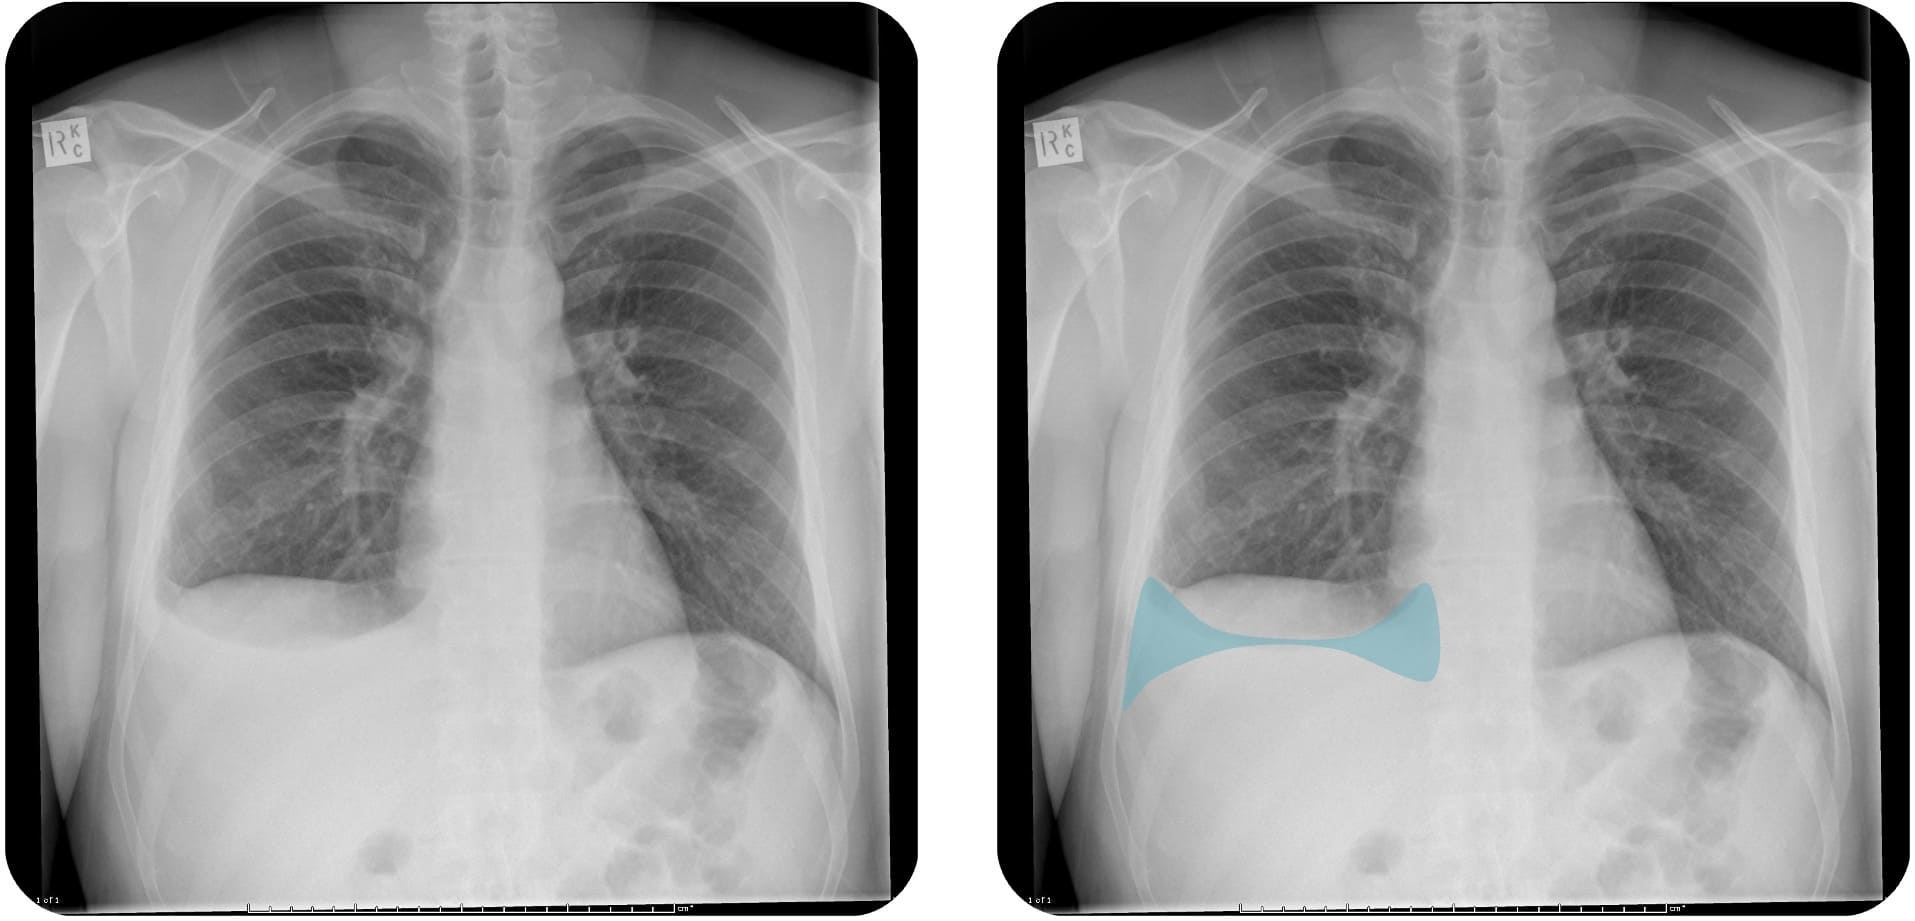

Im Röntgen-Thorax

Meniskuszeichen

Der Pleuraerguss

Case courtesy of Frank Gaillard, Radiopaedia.org, rID: 25595